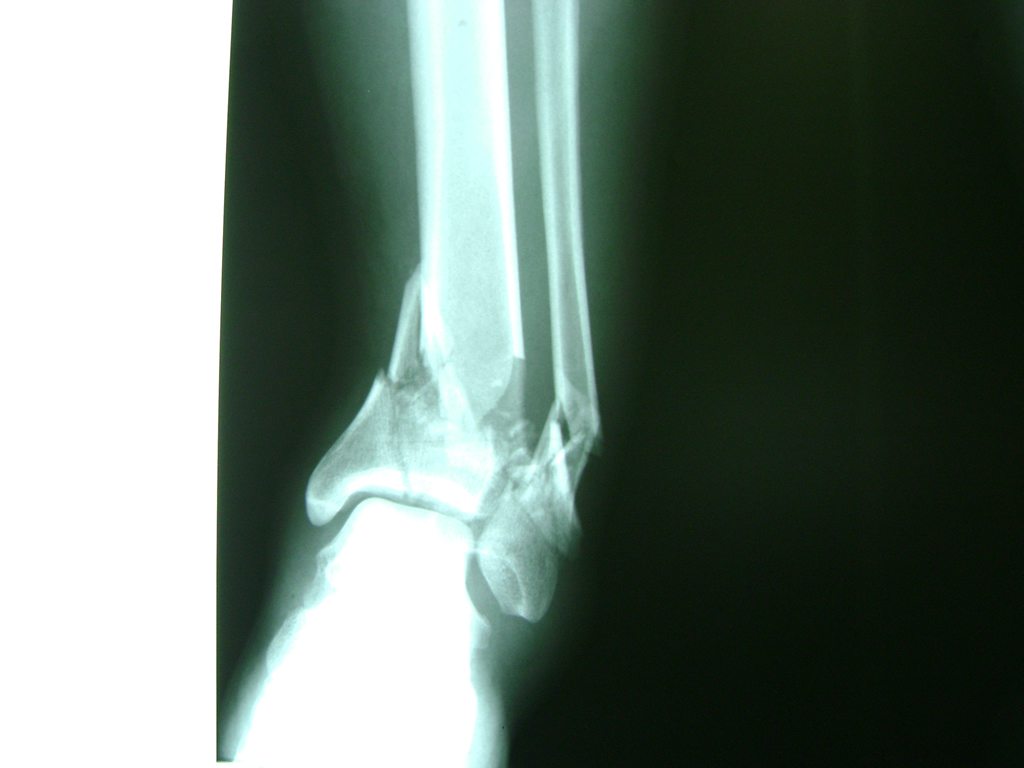

Una fractura de tobillo es la rotura de uno o más de los huesos del tobillo. Estas fracturas pueden ser:

Algunas fracturas de tobillo pueden requerir cirugía si:

- Los extremos de los huesos están desalineados entre sí (desplazados).

- La fractura se extiende hasta la articulación del tobillo (fractura intra-articular).

- Los tendones o ligamentos (tejidos que sujetan los músculos y los huesos entre sí) están rotos.

Cuando se necesita cirugía, es probable que esta implique el uso de clavijas de metal, tornillos o placas para sostener los huesos en su lugar mientras la fractura se consolida. Los elementos de soporte pueden ser temporales o permanentes.